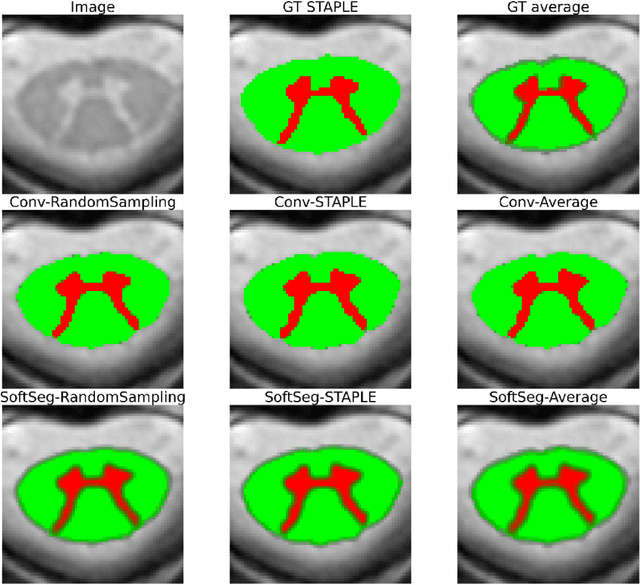

Abstract:Medical tasks are prone to inter-rater variability due to multiple factors such as image quality, professional experience and training, or guideline clarity. Training deep learning networks with annotations from multiple raters is a common practice that mitigates the model's bias towards a single expert. Reliable models generating calibrated outputs and reflecting the inter-rater disagreement are key to the integration of artificial intelligence in clinical practice. Various methods exist to take into account different expert labels. We focus on comparing three label fusion methods: STAPLE, average of the rater's segmentation, and random sampling of each rater's segmentation during training. Each label fusion method is studied using both the conventional training framework and the recently published SoftSeg framework that limits information loss by treating the segmentation task as a regression. Our results, across 10 data splittings on two public datasets, indicate that SoftSeg models, regardless of the ground truth fusion method, had better calibration and preservation of the inter-rater rater variability compared with their conventional counterparts without impacting the segmentation performance. Conventional models, i.e., trained with a Dice loss, with binary inputs, and sigmoid/softmax final activate, were overconfident and underestimated the uncertainty associated with inter-rater variability. Conversely, fusing labels by averaging with the SoftSeg framework led to underconfident outputs and overestimation of the rater disagreement. In terms of segmentation performance, the best label fusion method was different for the two datasets studied, indicating this parameter might be task-dependent. However, SoftSeg had segmentation performance systematically superior or equal to the conventionally trained models and had the best calibration and preservation of the inter-rater variability.